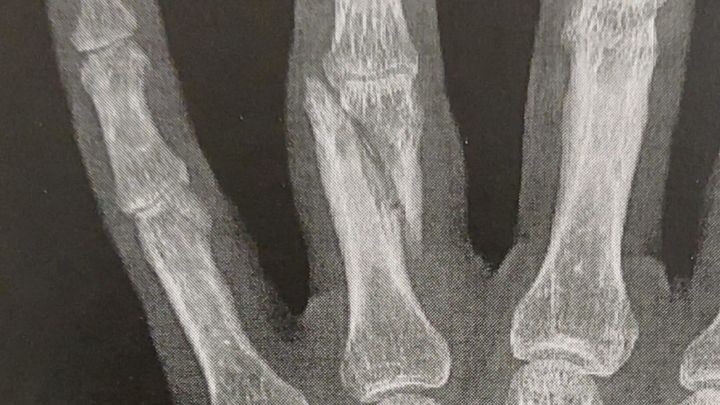

Il y a quelques jours, notre cher ami Jameel se faisait agresser violemment dans la rue pour ses positions politiques. C’est la 2e fois en un mois qu’il subit une agression raciste… Il a une double fracture à la main cette fois-ci, et il doit donc se faire opérer.

N’ayant pas de mutuelle, l’hôpital lui demande de régler un tiers de l’opération lui-même (+ de 500€)